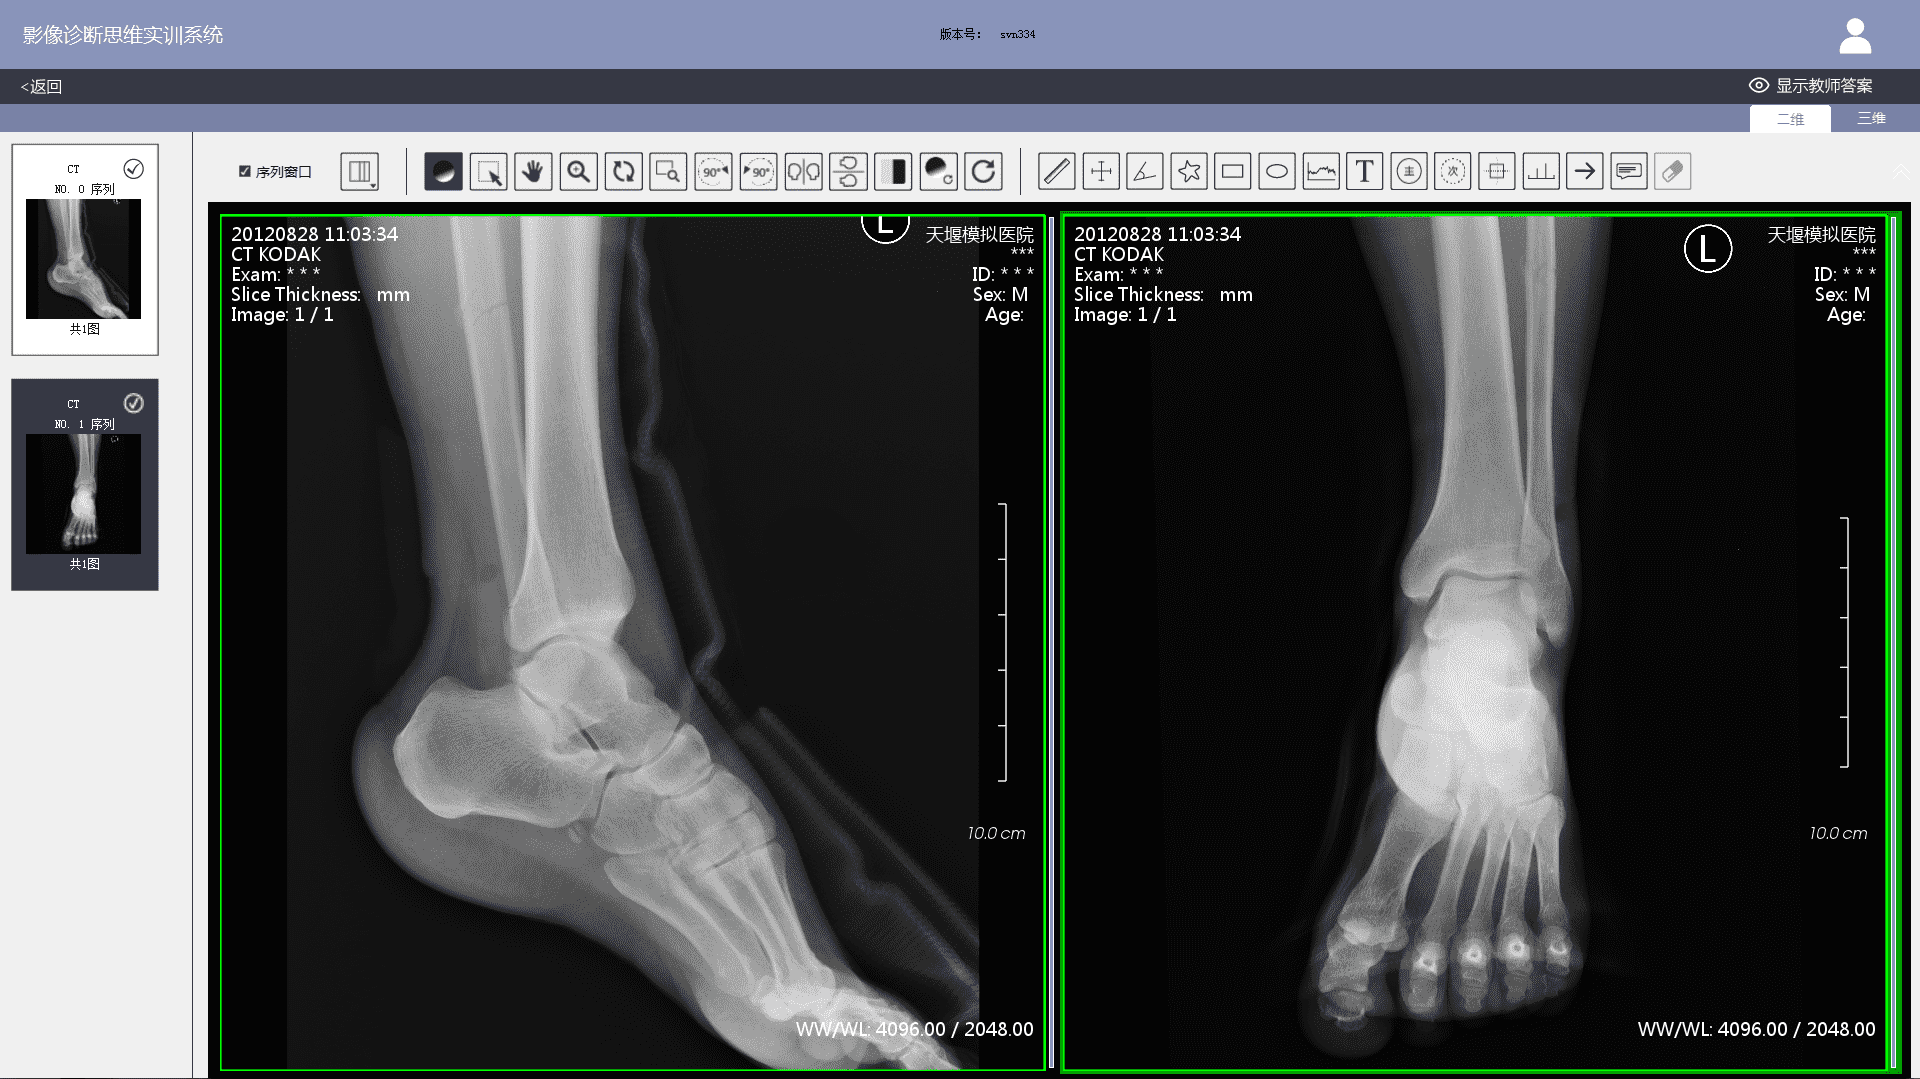

3) Imaging workstation: The system comes with an imaging workstation and all cases can be loaded with DICOM files. Teachers can post-progress them according to actual teaching needs. The post-processing function meets the basic requirements of a common clinical imaging workstation, including: 1) layout. Users can choose 1X1, 1X2, 2X1, 2X2, 2X3, 3X3, etc.; 2) Window width and level adjustments; 3) Zoom in and out; 4) Zoom in on the area of interest; 5) Left turn 90 degrees; 6) Right turn 90 degrees; 7) Left and right mirror flip; 8) Up and down mirror flip; 9) Negative film; 10) Distance measurement; 11) Two-way ruler; 12) Angle measurement; 13) Polygon measurement; 14) Adding notes & comments; 15) Labeling major signs; 16) Labeling secondary signs, etc.

3) When viewing case images, students can post-process DICOM files on the imaging workstation to observe positive and negative imaging signs in greater detail. After finishing a case exercise, student's test results, the correct diagnosis report and the comparison of the thinking processes will show. Students can also participate in image thinking case assessment set up by teachers.